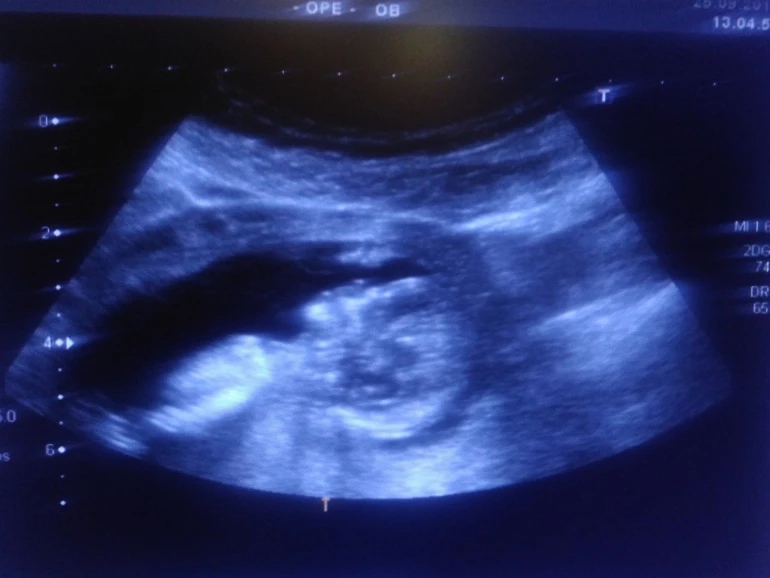

Активный такой мальчуган, еле рассмотрели все! Сказала врач, что редко такое бывает в 12 недель, но "причандал" серьезный, сказала, что сомнений нет-пацан, и показала со всех сторон папину радость))) лежит на спине, пинается ногами и сосёт палец.

Ну вот и позади первый скрининг 12+3, познакомился папа с пузожителем, все хорошо и закрашиваю значок- у нас мальчик!!! Ах, как папа счастлив, и слышать не хотел, что может быть девочка. По ходу сын услышал его мольбы и отрастил в первую очередь "началко", а теперь будет равномерно от "началка" расти))))))))) Почему началко?!- это муж мой так говорит, мол это у него не конец, а началко, он от него вверх и вниз равномерный)))))))))))))) Активный такой мальчуган, еле рассмотрели все! Сказала врач, что редко такое бывает в 12 недель, но "причандал" серьезный, сказала, что сомнений нет-пацан, и показала со всех сторон папину радость))) лежит на спине, пинается ногами и сосёт палец. Я конечно не знаю, что бы там не говорили за кишечник, но я со вчерашнего дня слышу возню именно в одном месте, уровень широкой резинки леггинсов, именно очень похоже на шевелюшки. Ну вот так и получилось, как я предполагала с самых первых дней, - будет мальчик - это они такие капризные))) не успела // увидеть, а уже кипишу сколько пережила, что в 7 недель казалось, что я уже недель 20 беременная, нервотреп казявоШный ))))))). Но все самое интересное ещё только впереди. А вот и папина гордость